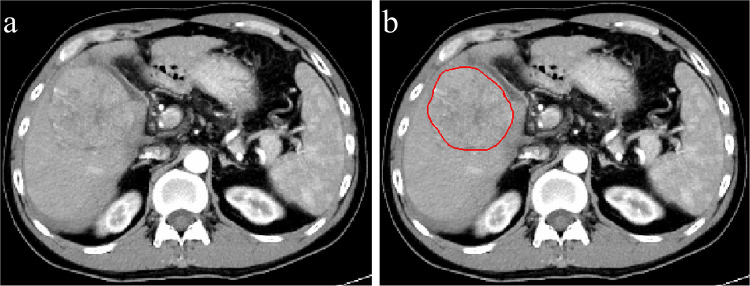

Purpose: This study aims to evaluate the advantages of the 2.5D deep learning-multi-instance learning (2.5D DL-MIL) model, based on CT arterial phase images, in predicting early recurrence (ER) of hepatocellular carcinoma (HCC) and examining the biological significance of MIL features.

Patients and methods: A total of 191 HCC patients were retrospectively included and categorized into ER (n=79) and non-early recurrence (NER, n=112) groups based on postoperative follow-up results. The patients were randomly divided to the training set (n=133) and validation set (n=58) in a 7:3 ratio. The predictive capabilities of the 2.5D DL-MIL model, Radiomics model, and Clinical model for ER of HCC were constructed and compared using CT arterial phase and clinical data. SHAP analysis was used to evaluate the contribution of MIL features in the model, and further analysis was conducted on the correlation between MIL features and microvascular invasion (MVI), Ki-67 expression, and pathological grading.